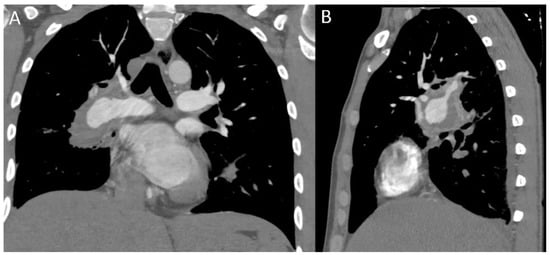

- Chae, E.J.; Do, K.H.; Seo, J.B.; Park, S.H.; Kang, J.W.; Jang, Y.M.; Lee, J.S.; Song, J.W.; Song, K.S.; Lee, J.H.; et al. Radiologic and Clinical Findings of Behçet Disease: Comprehensive Review of Multisystemic Involvement. Radiographics 2008, 28, 1–56. [Google Scholar] [CrossRef]

- Ceylan, N.; Bayraktaroglu, S.; Erturk, S.M.; Savas, R.; Alper, H. Pulmonary and Vascular Manifestations of Behcet Disease: Imaging Findings. AJR Am. J. Roentgenol. 2010, 194, W158–W164. [Google Scholar] [CrossRef]